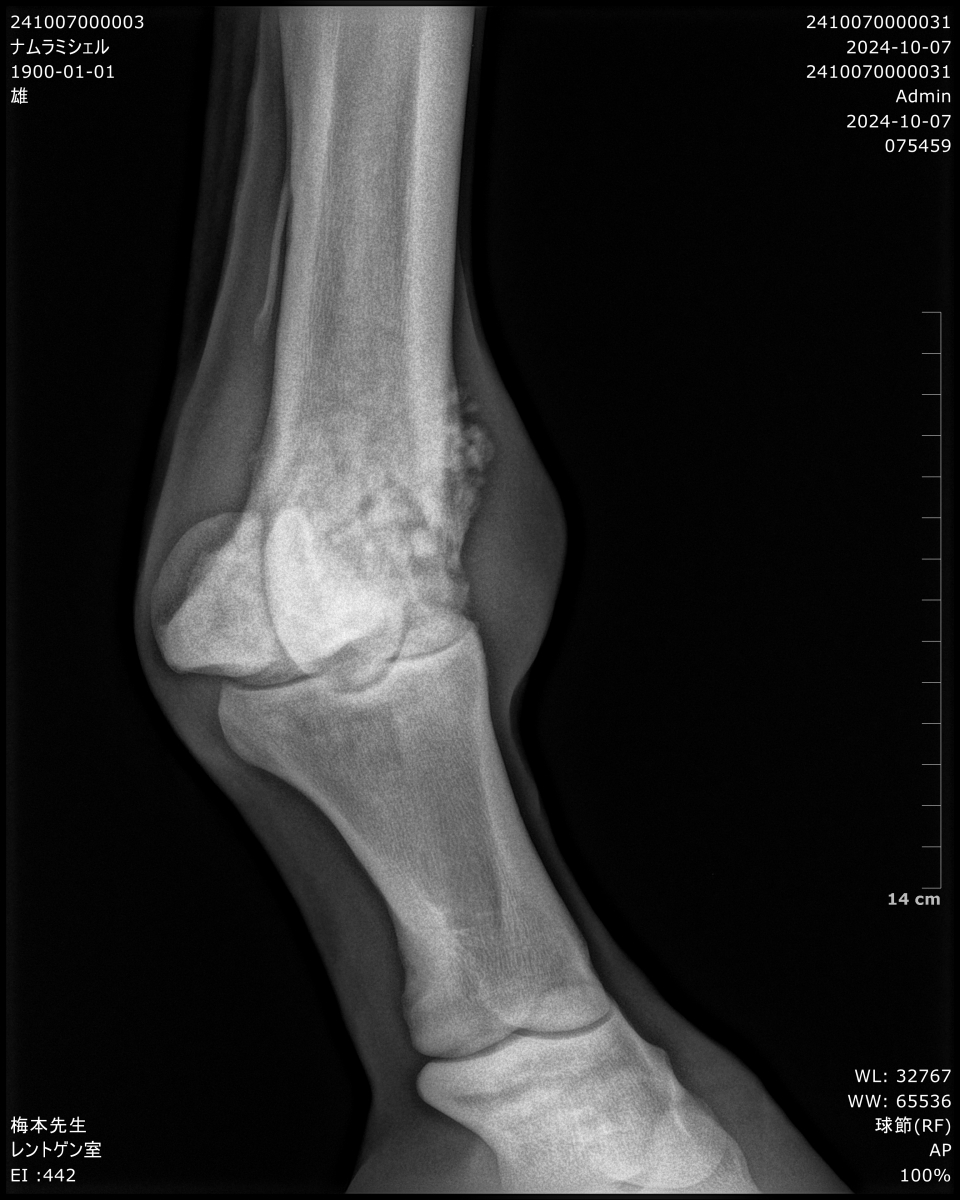

・2024/10/07 入厩前の放牧先である茨城・ケイワンステーブルにて歩様が乱れたためレントゲン検査を行ったところ、以前より腫れを指摘されていた右前の球節部分に骨膜が出ていることが確認。骨膜が大きく出ており、治療を行ったとしても復帰までには相応の時間がかかることから、10/10のサラオクに出品することで共有馬主間で合意。